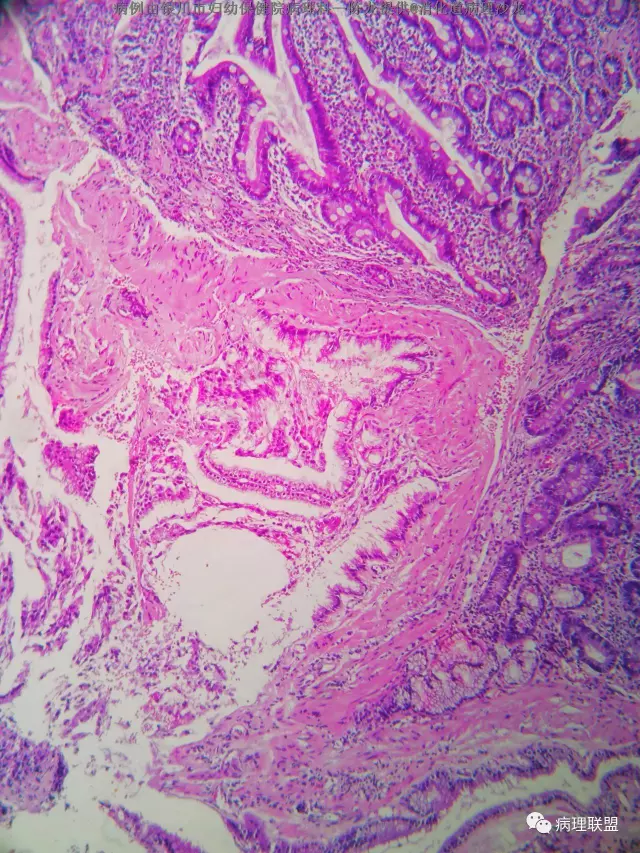

男性 68 十二指肠息肉 大小约3个0.4

(病例由银川市妇幼保健院病理科—陈龙提供,致谢!)